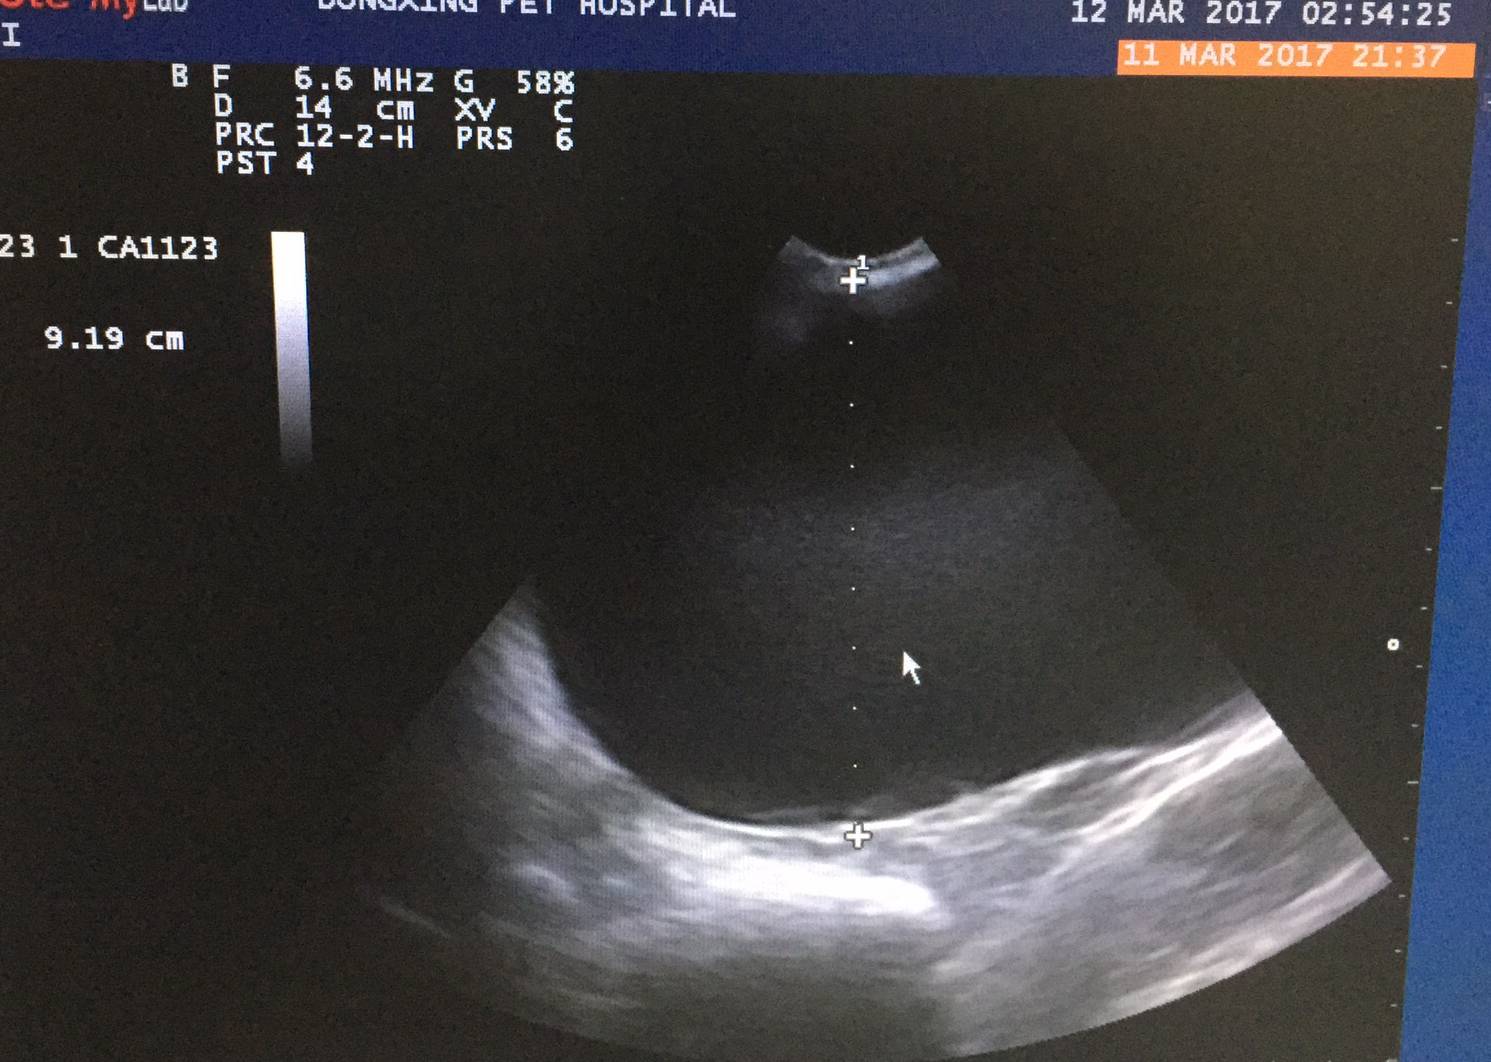

经过实验室及影像学检查,查找发病原因及体况评估:

根据临床检查结合实验室影像检查结果分析:

a疑似左侧肾脏囊肿,卵巢囊肿,乳腺肿瘤,重度牙结石,肺脏情况尚可,心脏肥大,阴道增生,血液学结果尚可,凝血机制尚可

初步诊断:疑似左侧肾脏囊肿(肿瘤?),乳腺肿块(肿瘤?)卵巢囊肿(肿瘤?),阴道增生,白内障。

常规术前准备,一级疼痛管理,麻醉管理,常规手术开腹后发现左肾囊肿性病变,增大,右肾尚可,双侧卵巢囊肿,经过分离结扎,摘除了病变囊肿及子宫卵巢,之后行双侧乳腺全切术。手术时间进行3.5小时,术中麻醉疼痛管理,狗狗体征相对稳定。